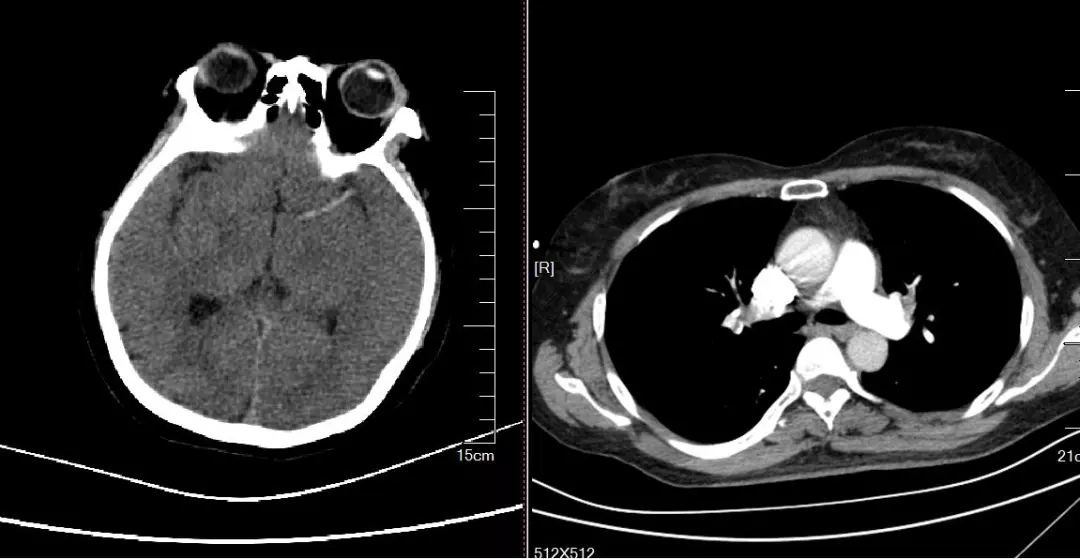

在与患者家属紧急沟通后,立即行CT下肺动脉造影及颅脑CT检查,结果印证了多学科会诊判断的准确性。

肺栓塞合并脑栓塞